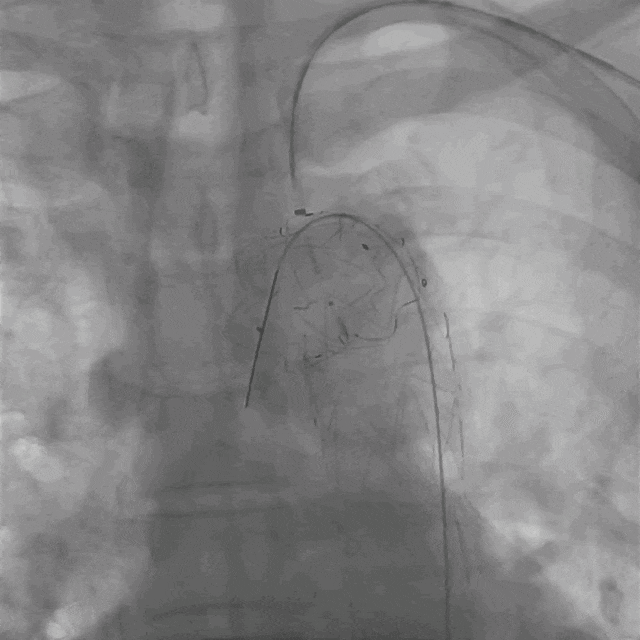

03. 左侧肱动脉采用0.018"导丝配合0.035"支撑导管顺利破膜,先后引入4*30mm球囊、7*80mm球囊、MUSTANG 8*40mm球囊扩张开窗口。

泥鳅导丝怎么用曲乐丰教授团队:0.018"和0.035"普通泥鳅导丝行胸主动脉弓上分支原位开窗的病例分享_https://www.jmylbn.com_新闻资讯_第13张

0.018"导丝配合0.035"支撑导管顺利破膜